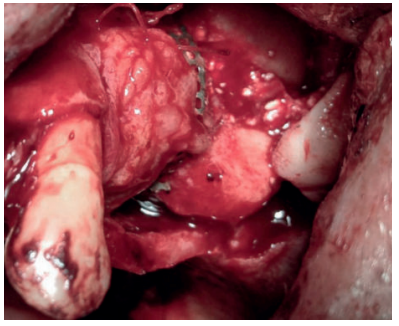

En el presente artículo se pretende mostrar la evidencia clínica de la efectividad del uso del colgajo pediculado de rotación palatina como método válido para evitar la exposición de la malla de titanio durante la regeneración ósea guiada.

This article aims to show the clinical evidence of the effectiveness of using the palatal rotated pedicle graft as an effective method to avoid exposing the micromesh during guide bone regeneration procedure.

Una buena técnica en aquellas zonas susceptibles de sufrir necrosis óseas o dehiscencias mucosas es el uso de un colgajo pediculado de tejido conectivo palatino, resultando ventajoso en diferentes métodos de aumento óseo maxilar, con o sin membranas1,2 .

El objetivo de este caso clínico es mostrar la evidencia clínica de la efectividad del uso del colgajo pediculado de rotación palatina como método efectivo para evitar la exposición de la malla de titanio durante la regeneración ósea guiada.